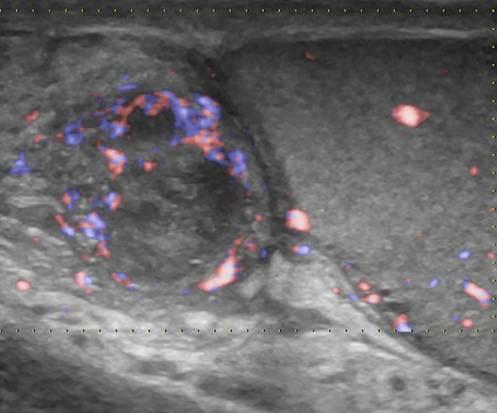

Viêm mào tinh hoàn

» Thông tin: Nam giới – 39 tuổi.

» Lâm sàng: Sưng đau vùng bìu.

# Viêm mào tinh hoàn apxe hóa.